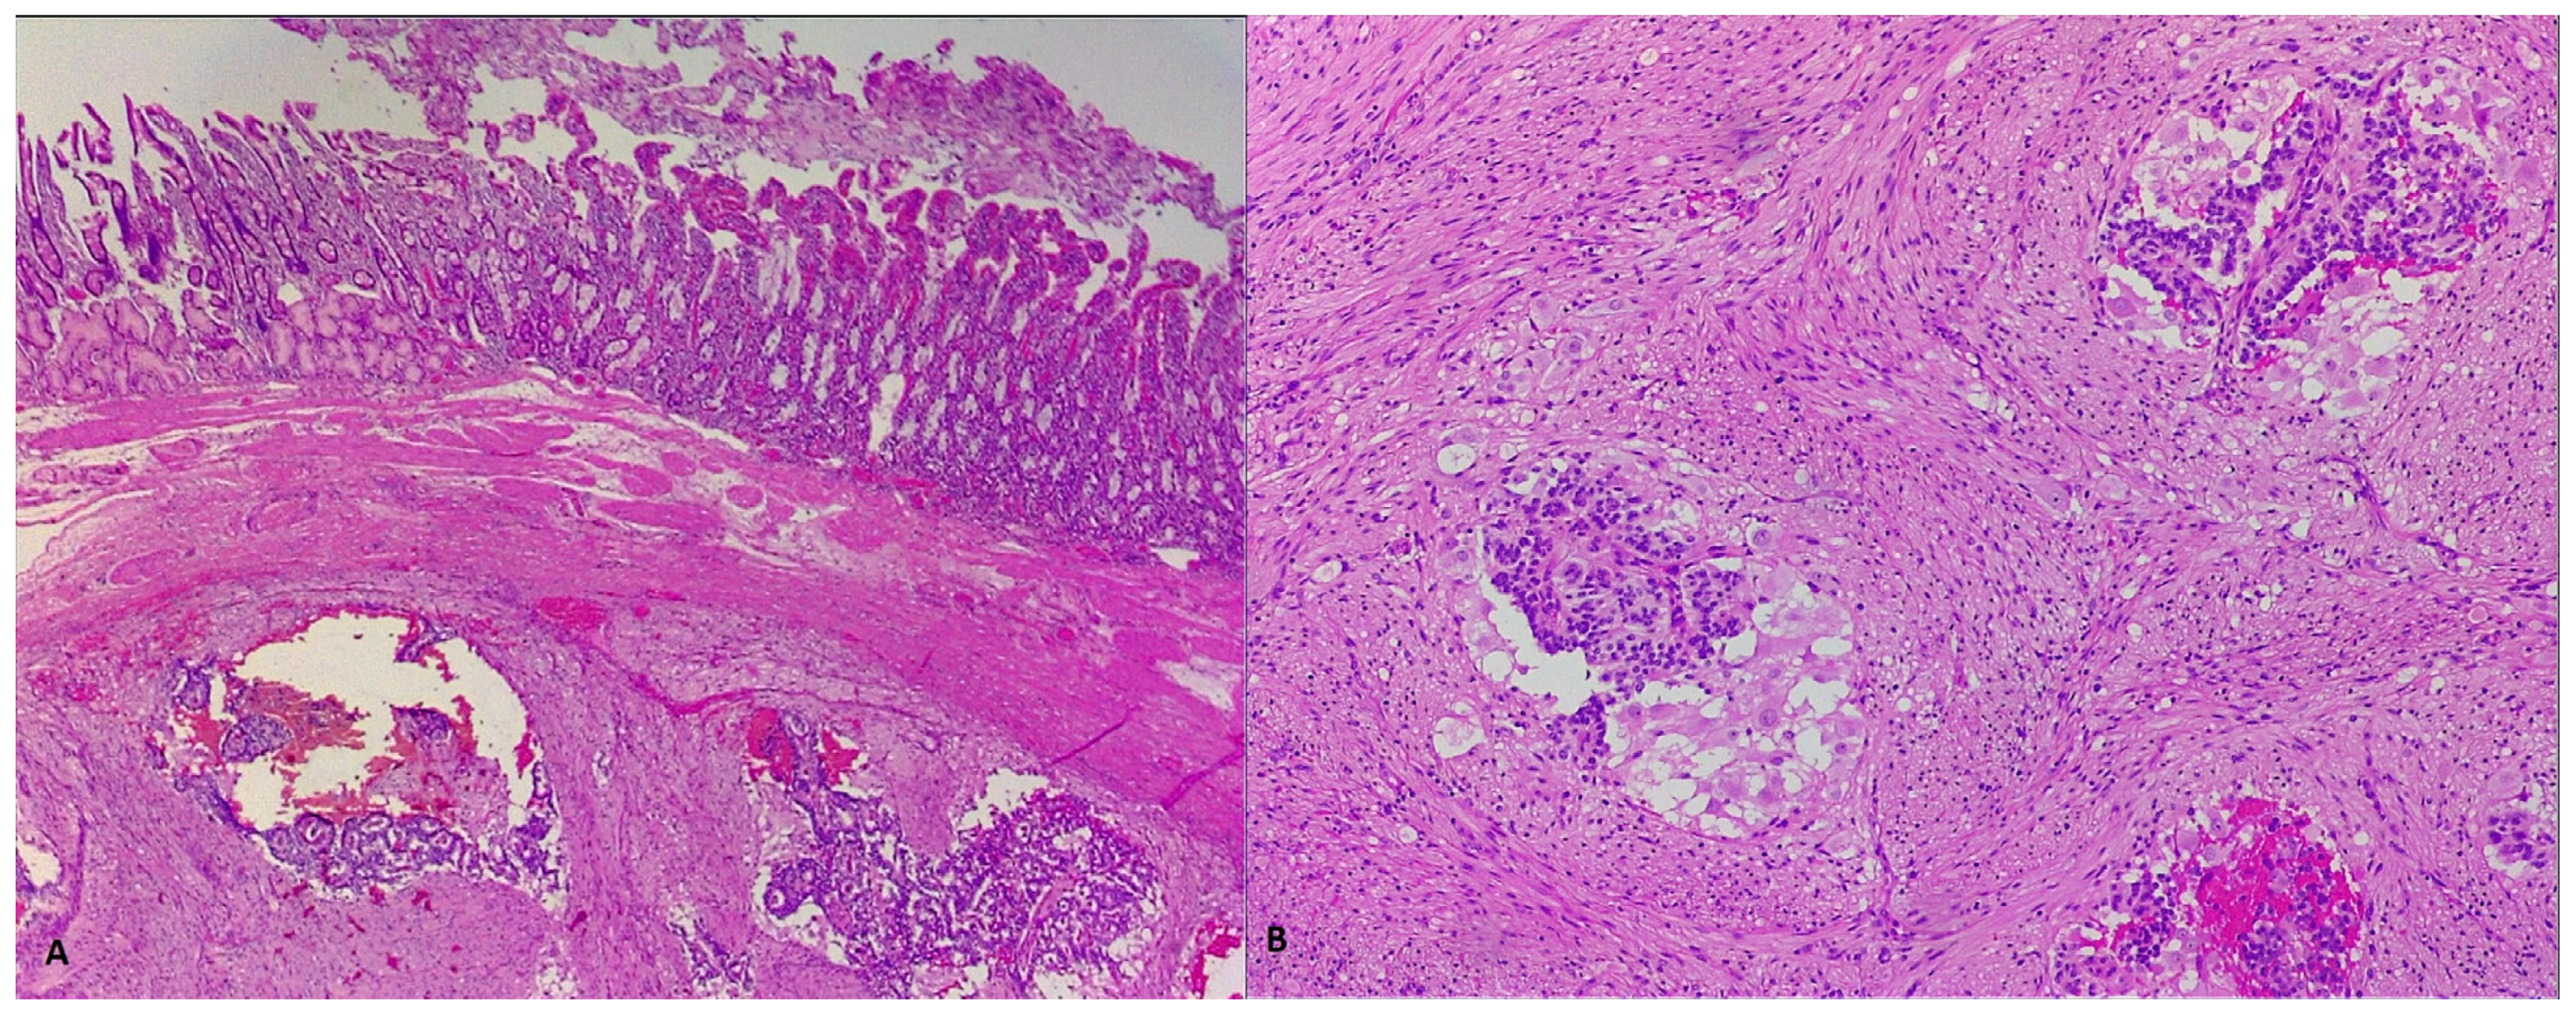

2. Case Report 1

3. Case Report 2

4. Case Report 3